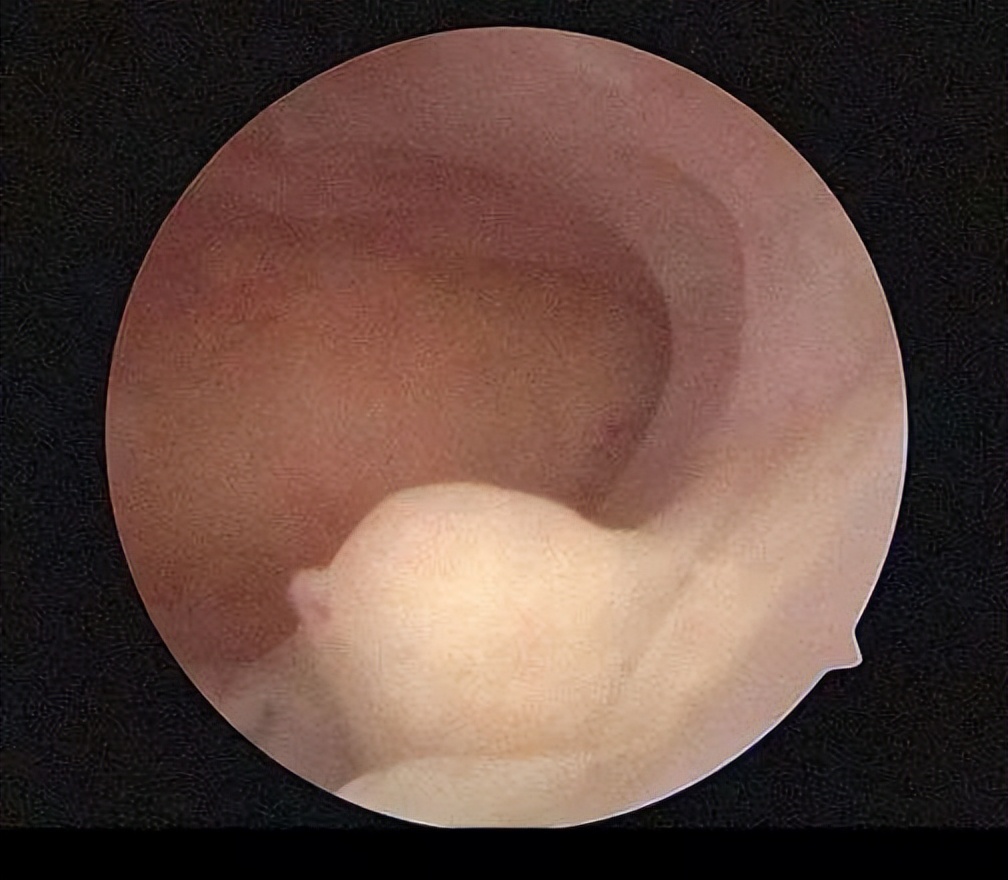

大概两个月前,有个二十多岁的小姑娘来找我,说:医生,我查出来子宫有好几个息肉,最大的一公分了,我很害怕,我不想手术,息肉会不会自己消失啊。

很多人检查出什么内膜增生,内膜息肉,就会开始害怕,西医给出的建议就是手术,但手术又会面临损伤子宫和复发的问题,难道只能手术吗,并不是!

我看了她的情况说:子宫内膜息肉不会自己消失,它是由于炎症、异物刺激、雌激素水平过高等因素导致子宫内膜局部过度增生所致,手术的话是会容易复发的,你的息肉数量多,都不是特别大,现在是要通过饮食和中药调理来控制其增长,才能慢慢清理掉。